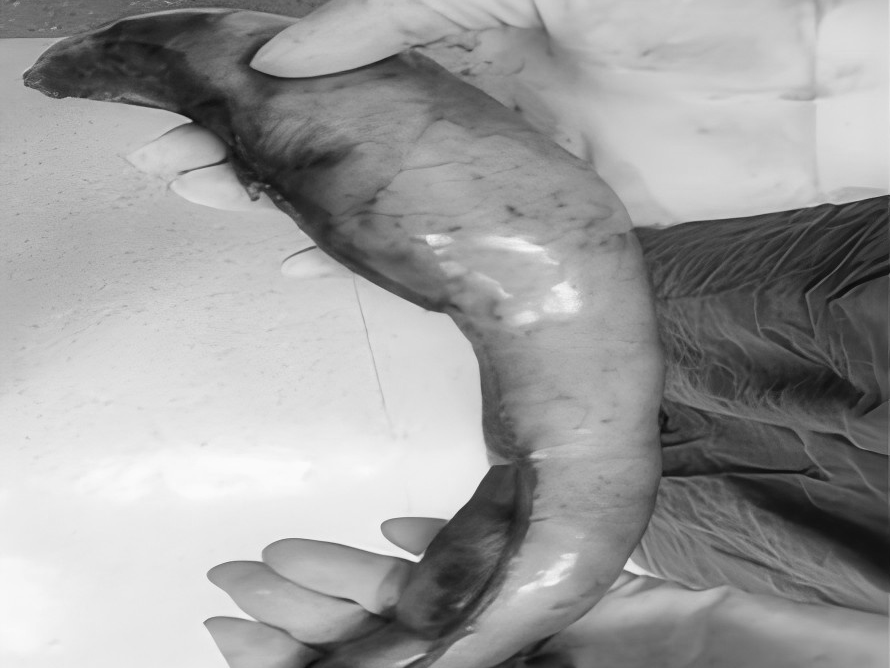

直肠脱垂是指直肠壁的一部分或全层向下移位,最终可能脱出肛门外的疾病。它并非肿瘤,但在老年人、多次分娩的女性、长期便秘或慢性咳嗽等腹压增高人群中较为常见。 【关键诱因与表现】 直肠脱垂主要因盆底肌肉、韧带等支撑结构松弛,加之长期腹压增高(如用力排便、慢性咳嗽、排尿困难)诱发。患者常感肛门坠胀或异物感,典型表现为排便或久站后有柔软肿物自肛门脱出,初期或可自行缩回,后期常需手法复位,并可伴排便困难、不尽感、肛门黏液或血性分泌物、潮湿瘙痒,严重者可能出现排便控制困难。 【治疗选择因人而异】 保守治疗(轻度或早期): 核心是消除诱因: 积极改善便秘(高纤维饮食、充足饮水、必要时遵医嘱用药)、控制咳嗽、解决排尿困难。 生活方式调整: 避免久蹲、久站、负重及用力排便。 盆底肌锻炼(凯格尔运动): 坚持锻炼有助于增强盆底支撑力。 及时复位: 轻柔地将脱出部分复位,防止卡住肿胀。 手术治疗(中重度或保守无效): 当脱垂严重影响生活、难以复位、反复出血或出现排便失禁等情况时,医生会评估手术的必要性。 手术目标是修复薄弱的支撑结构,将直肠固定在正常位置。有多种手术方式(包括微创方法),医生会根据个体情况选择最合适的方案。 【重在预防与管理】 预防的关键在于减少腹压增高因素: 1.保持大便通畅,避免用力排便。 2.积极治疗慢性咳嗽、前列腺增生等导致腹压增高的疾病。 3.坚持规律进行盆底肌锻炼。 4.维持健康体重,避免长期重体力劳动。 直肠脱垂虽然带来不适,但通过及时就医、明确诊断并接受规范治疗(包括生活方式调整和必要的医疗干预),多数患者的症状可以得到有效控制,生活质量显著提升。如有相关疑虑,建议咨询肛肠专科医生。 注:部分图片来源于网络,如有侵权,请联系删除。 贵州航天医院普外科专家简介 高大勇 普外科(肛肠外科)学科带头人、名誉主任,主任医师、教授 临床擅长:对中西医结合诊治肛肠学科各种常见病、多发病及疑难杂症等具有丰富的临床经验。 原遵义市第一人民医院(遵义医科大学第三附属医院)、遵义市中医院肛肠科主任。中华中医药学会肛肠分会常委,全国中医肛肠学科名专家,中国健康促进与教育协会肛肠分会常委,中国康复医学会肛肠疾病康复专业委员会常委,中国民间中医医药研究开发协会肛肠分会副秘书长,中国医师协会中西医结合肛肠医师专业委员会常委,国家二级心理咨询师,贵州省第一批中医名医工作指导老师,遵义市名中医,遵义市肛肠学会会长,遵义市肛肠质控中心名誉主任,遵义市中西医结合学会名誉会长,遵义市健康科普专家,原贵州省中西医结合学会肛肠分会副主任委员、贵州省中医肛肠质控中心副主任、遵义市医学会医疗鉴定委员会专家、遵义市卫生系列高评委。发表论文30余篇,主编和参编医学著作5本,主持省级科研课题2项、市级科研课题2项、院级科研课题1项。 梁 跃 中共党员,普外科党支部书记、主任,主任医师 临床擅长:对普外科各类肿瘤手术具有丰富的临床经验。 毕业于遵义医学院,遵义市医学会小儿外科学分会常务委员,遵义市肛肠协会理事,遵义市医学会核医学分会(第二届)委员会委员;荣获第三期“黔医人才计划”优秀学员称号;主持市级课题1项,完成省级课题1项,在国内各类刊物上发表论文10余篇。 钱科洪 民盟盟员,普外科副主任医师 临床擅长:从事普外科临床工作30余年,对各类普外科疾病的诊治、乳腺、甲状腺、胃十二指肠、结直肠等疾病及疑难杂症具有丰富的临床经验。 毕业于遵义医学院临床医疗系,2009年前往中山大学附属第一医院微创外科进修学习,在国内各专业期刊发表论文数篇。 贵州航天医院普外科简介 基本情况 贵州航天医院普外科成立于1968年,前身属于航天部O61基地3417医院外一科,1998年3417医院、3427医院合并后更名为普外科,下设胃肠外科、肛肠外科2个亚专业科室,拥有在全市较为先进的专科设备和技术,是中国疝病专科联盟单位,贵州医科大学附属医院胃肠外科专科联盟单位。开放床位40张,配备医护人员21人。 专科特色 普外科致力于胃肠及肛肠疾病的外科临床诊治及科研,以腹腔镜微创外科技术为本,形成以快速康复治疗胃肿瘤、结直肠肿瘤、小肠肿瘤、直肠脱垂、肥胖病、急腹症、各类疝、痔、瘘等专科特色,同时注重胃肠疾病尤其是结直肠恶性肿瘤的基础研究和临床转化研究,总体诊断和治疗水平在区域同级医院居于领先水平。 开展手术:腹腔镜下胃癌根治术,腹腔镜下袖状胃切除术,腹腔镜下胃肠道间质瘤切除术,腹腔镜下结、直肠癌根治术,胃癌、结直肠癌的精准治疗,腹腔镜下小儿疝气、成人疝修补术,腹腔镜下阑尾手术,内痔的硬化注射治疗及痔疮的微创治疗:ATH、PPH、TST,直肠脱垂的各种手术治疗,难治性伤口VSD技术,鼻胃肠管、肠梗阻导管置入术,肛肠术后间歇性导尿技术,并引进了中医适宜技术,也为各种化疗患者提供输液港安装,提高患者就医体验。 腹腔镜下腹股沟疝 无张力修补术 腹股沟疝里金斯坦(Lichtenstein)手术 PPH微创术治疗环状混合痔 黏连性或炎性肠梗阻-肠梗阻导管 腹腔镜袖状胃切除 腹腔镜阑尾切除术 腹腔镜阑尾肿瘤切除术 腹腔镜下结肠癌根治术 诊疗范围 胃肿瘤、结直肠肿瘤、小肠肿瘤、肥胖症、各类急腹症、腹部外伤、腹壁疝、便秘、直肠脱垂、痔疮、肛瘘、肛裂等胃肠、肛肠外科疾病。 END